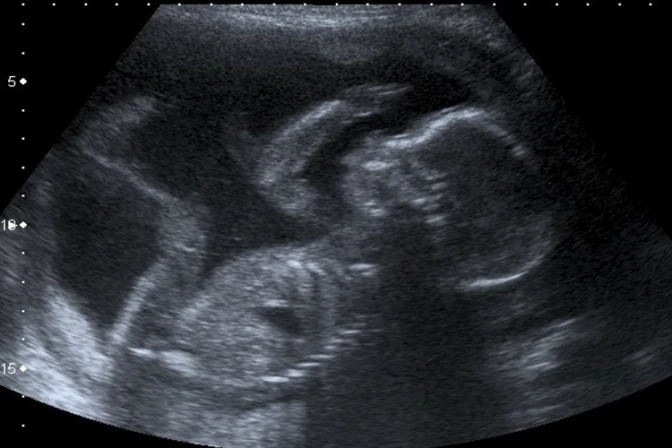

En diciembre de 2011, se practicó al aborto a la embarazada en la clínica El Sur Atocha Clínica Ginecológica de Sevilla, mediante una punción. Según precisan, ginecólogo "prescindiendo de las más elementales medidas de precaución que exige pericia médica, practicó la punción sin cerciorarse antes de cuál era el feto enfermo, pinchando el feto sano, error que pudo haber evitado tomando las elementales medidas de comprobación ecográfica de la posición de ambos fetos".

Según los datos que aporta el diario ABC, en enero de 2012, en el hospital Puerta del Mar de Cádiz, se descubrió mediante una ecografía, que la punción había sido practicada 'al feto sano'.